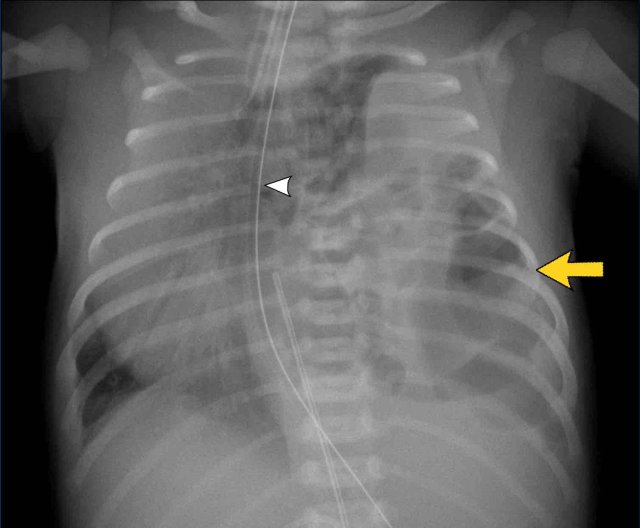

One day old neonate, 29 weeks of gestational age.

Image

• Hyperinflation due to CPAP.

• Granular opacification of both lungs with air bronchograms.

• NG tube in good position.

• Vessels and cardiac silhouette are harder to distinguish.

Conclusion: RDS grade 2.